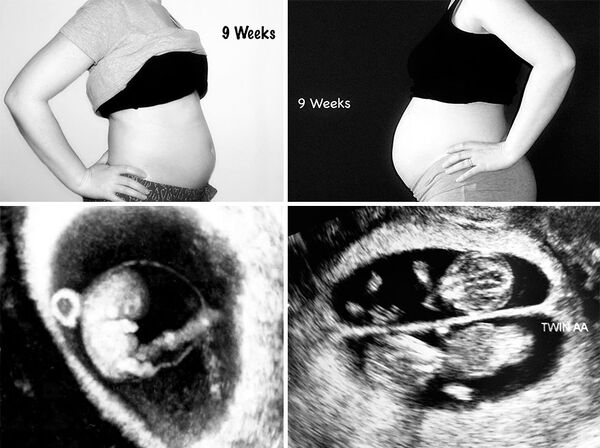

Janet daha önce düşük yapmış, polikistik over sendromu tedavisi görmüş ve sonunda hamile kalabilmiş bir umut örneği! Önce bir kızı ve daha sonra ikizleri olan Janet, iki hamileliğini fotoğraflar aracılığıyla karşılaştırmış. İlk fotoğraflar Janet tek kızına 9 haftalık hamileyken, ikincisi ise ikizlere.

Burda ise Janet 12 haftalık hamile, sağ taraftaki fotoğraf ikizlere ait!